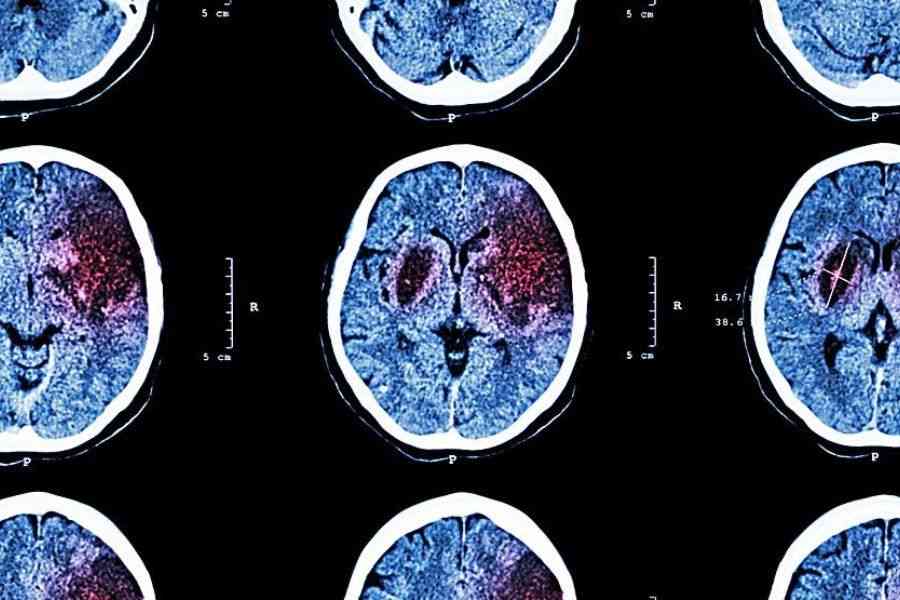

İnsultlar daha çox 55 yaşdan aşağı qruplarda olur

55 yaşdan kiçik insanlar arasında insultlar getdikcə daha çox yayılır.

“Medicina” xəbər verir ki, Melburn Universitetinin alimlərinin fikrincə, 55 yaşdan yuxarı insanlarda insultların qəribədir ki, sayı azalır. Lakin gənclər arasında vəziyyət fərqlidir.

Klinik təcrübə göstərir ki, inkişaf etmiş ölkələrdə insultların sayı artır, lakin müxtəlif yaş qrupları üzrə statistikaya daha yaxından baxdıqda təəccüblü bir mənzərə ortaya çıxır.

İngilisdilli ölkələrdə 55 yaşdan yuxarı insanlar arasında insultların sayı azalır, gənclər arasında isə artmaqdadır. Dünyada ən uzun əhaliyə əsaslanan insult tədqiqatlarından biri aparılıb; onun müəllifləri İngiltərənin Oksfordşir şəhərinin bütün əhalisini - 100.000 nəfərdən bir qədər az insanı izləyiblər.

Kohort kiçik olsa da, insult keçirən bütün şəxslər tam nəzarətdə saxlanılıb.

Bunu böyük şəhərlərdə və ya əhali arasında etmək mümkün deyil. Zamanla insult nisbətləri haqqında dəqiq məlumatlar əldə edilib. Məlum olub ki, yaşlı insanlarda insult halları hazırda daha az müşahidə olunur, çünki onlar özlərini daha yaxşı qoruyur və profilaktikaya daha çox diqqət yetirirlər.

Bununla belə, gənclər arasında insult hallarının yayılması artır, çünki onlar sadəcə yaşlarında beyin-damar qəzası keçirə biləcəklərinə inanmırlar.

İnsult halları 55 yaşdan kiçik insanlar arasında getdikcə daha çox müşahidə olunur.

10 saatlıq iş günü insult riskini artırır.

Həmçinin məlum olub ki, insult halları daha yüksək peşəkar standartlara malik şəxslər arasında daha çox müşahidə olunur. Bu, rəhbər vəzifələrdə çalışanlara da aiddir. Lakin fiziki əməklə məşğul olanların insult nisbəti daha aşağıdır. Menecerlər və rəhbərlər, ehtimal ki, işdə daha çox stress yaşayır və fiziki əməklə məşğul olanlara nisbətən daha az fiziki fəaliyyətlə məşğul olurlar.